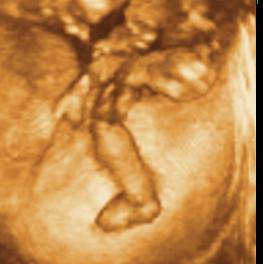

Ui.: Kedden megyünk genetikai UH-ra, szorítsatok nekem. Aztán majd jelentkezem.